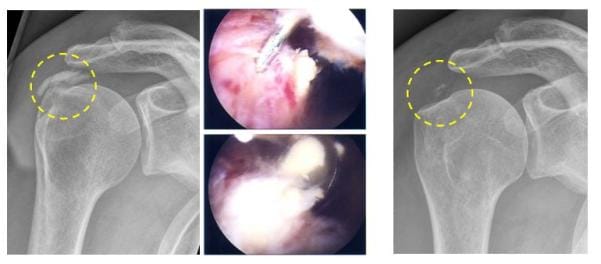

Röntgenbild die Kalkablagerungen in der Sehne werden bei einer Arthroskopie entfernt

Die Kalkablagerungen in der Sehne (linkes Röntgenbild, gelber Kreis) werden bei einer Arthroskopie entfernt (mittlere Bilder), die Röntgenkontrolle (rechtes Röntgenbild, gelber Kreis) zeigt die weitgehende Kalkentfernung. (Bilder: Orthopädie)